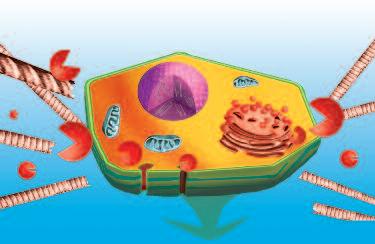

Il processo di ovulazione nel corpo femminile è una delle funzioni più affascinanti in cui il corpo utilizza un meccanismo di dissoluzione del collagene. I cambiamenti ormonali mensili del ciclo femminile stimolano certi tipi di cellule (granulociti) che circondano la cellula uovo in fase di maturazione all'interno dell'ovaio (follicolo).

In condizioni di normali, stimolati dagli ormoni (ad esempio gli estrogeni), i granulociti iniziano a produrre liquidi ricchi di questi enzimi che dissolvono il collagene. Questo avviene a metà del ciclo mestruale femminile, la cellula uovo matura è circondata da questi enzimi che dissolvono il collagene, per cui il collagene della parete ovarica si assottiglia fino a formare un buco. Questa apertura è abbastanza grande solo per permettere alla cellula uovo di passare dalle ovaie attraverso il piccolo canale di collegamento (trombe di Falloppio o tube ovariche) nell’utero.

E' chiaro che questo meccanismo deve essere perfettamente sincronizzato e limitato a questa specifica ubicazione. Questo meccanismo deve far sì che una sola cellula uovo per ogni ciclo mestruale passi e inizi il suo viaggio verso l'utero. Pertanto, è assolutamente importante che gli enzimi di dissoluzione del collagene entrino in azione quando sia necessario e solo in una specifica ubicazione, dove poi il meccanismo che blocca questi enzimi avvia l’auto-guarigione del tessuto.

Subito dopo che la cellula uovo ha lasciato l’ovaio, l'attività degli enzimi che dissolvono il collagene è fermata da altri blocchi enzimatici del corpo, che riequilibrano i meccanismi di produzione di collagene, poiché hanno la meglio sul processo di dissoluzione dello stesso. Utilizzando questo meccanismo, il tessuto della parete dell'ovaio può guarire e chiudersi rapidamente. Quattro settimane dopo, l'intero processo si ripete.

Questo accade nella parete dell’ovaio

L’ovulo inizia la sua migrazione verso l’utero

La produzione di enzimi che digeriscono il collagene, stimolata dagli ormoni, fende il tessuto dell’ovaio per alcuni secondi – il tempo necessario affinché la cellula uovo matura lasci l’ovaio e possa migrare nell’utero.

L’immagine A mostra il momento in cui la cellula uovo matura lascia l'ovaia, attraverso un piccolo foro biologicamente creato nelle pareti di questo organo Gli enzimi che digeriscono il collagene (pacmen rossi) vengono aggiunti per illustrare questo processo biologico

L’immagine B mostra una cellula uovo (al centro) vista ad un microscopio molto potente. I piccoli dossi che circondano questa grande cellula sono le cellule (granulociti) specializzate nella produzione di grandi quantità di enzimi che digeriscono il collagene necessario per l'ovulazione.